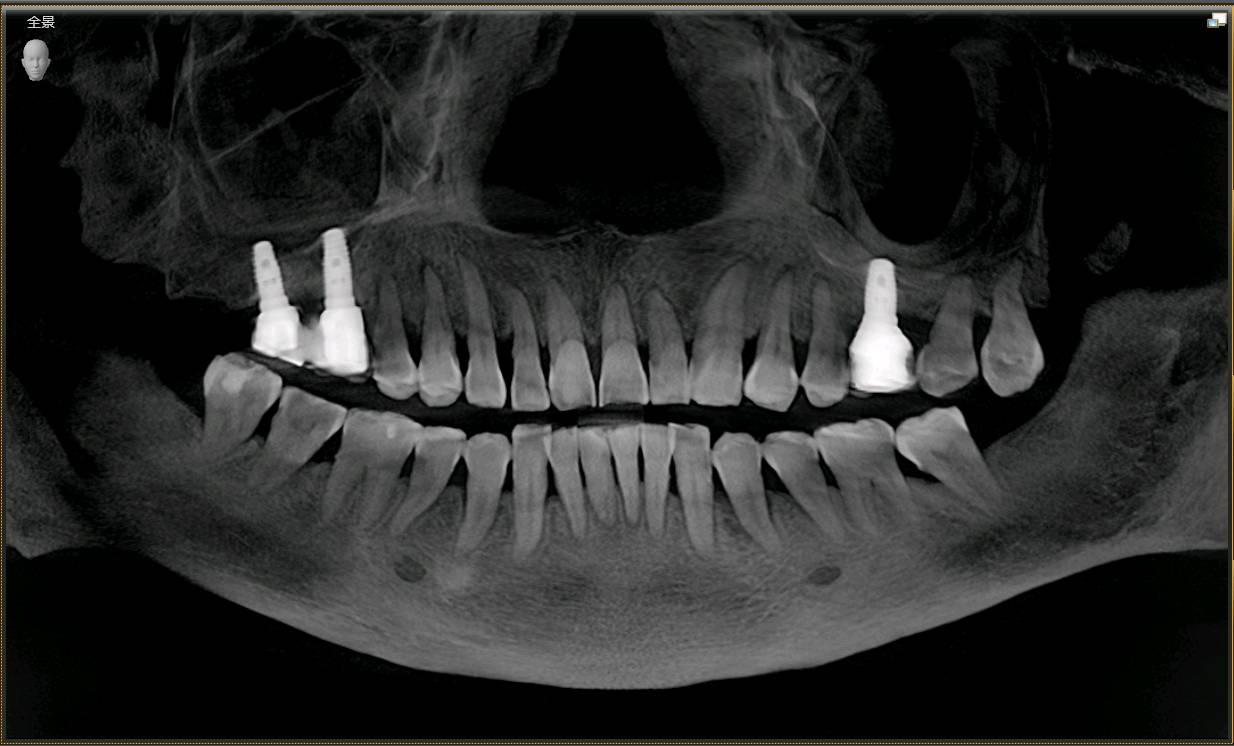

患者女,65 岁。右上 6、7 已做过两颗种植牙,因右上 5 松动,影响咀嚼,要求治疗。 口腔检查:右上 67 种植牙存,右上 5 叩诊+,探诊深牙周袋,冷热无反应,龈周-。X 线示 根尖周大面积阴影,颌面可见近远中折裂。诊断慢性根尖炎,牙根折裂。无法保留,建议拔除后,种植修复。

患者知情并同意治疗。抽静脉血30ml,制作CGF,0.1%聚维酮碘溶液口内粘膜消毒,0.5%聚维酮碘溶液口外皮肤消毒,4%盐酸阿替卡因肾上腺素注射液2.0ml浸润麻醉,牙槽嵴顶切开粘骨膜,翻瓣,见腭侧大面积骨缺损,球钻定位,先锋钻导向,骨质钻扩大种植窝,并攻丝,植入法国安卓建种植体4.0*10mm,上覆盖帽,腭侧骨缺损区植入bio-oss骨粉0.5g及CGF,并盖bio-Gide膜及CGF膜,严密缝合,常规医嘱,15天拆线。

进行 5 号牙种植术中

植入后 X 线照片